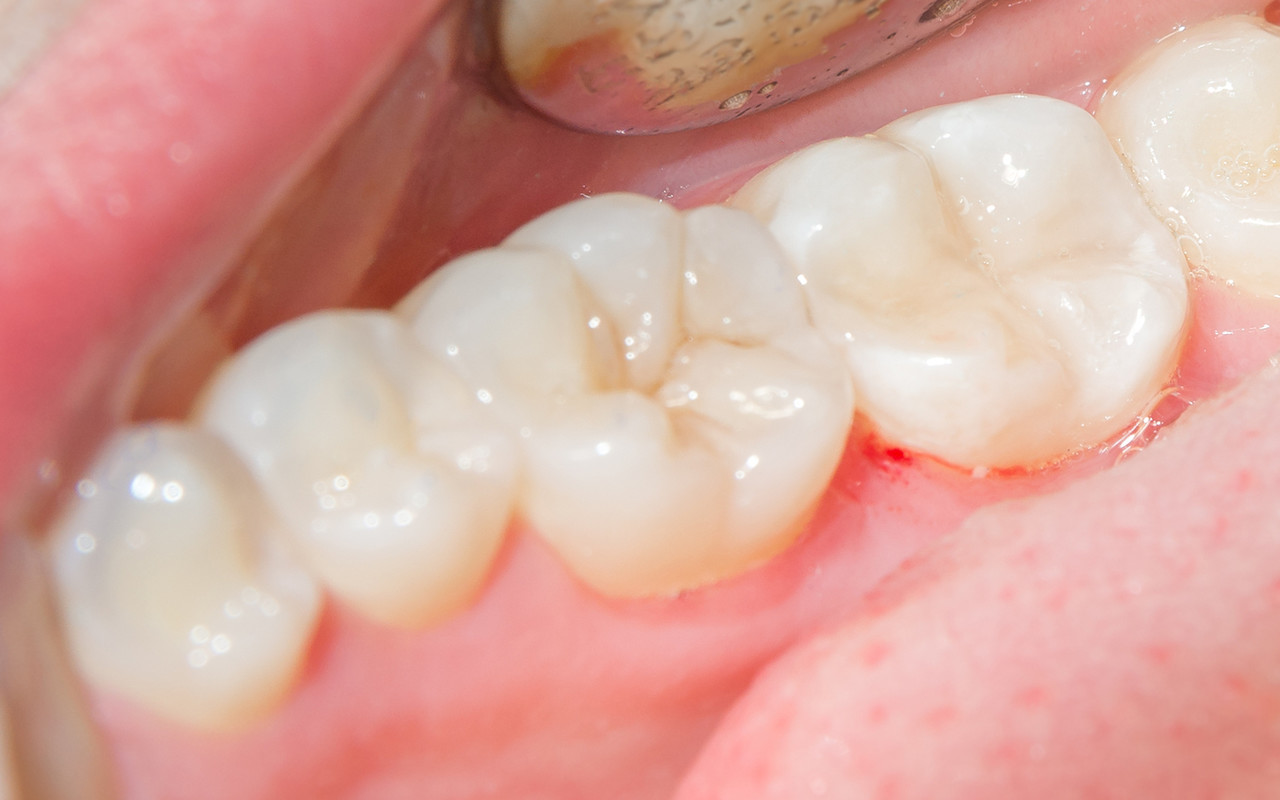

STEP 02. 교합면에서 잇몸 경계까지 진행된 균열

증상 : 씹을 때 찌릿한 통증이 있을 수 있습니다.

치료 : 치아가 쪼개지는 것을 막는 크라운 치료가 필수입니다.

필요한 경우 신경치료가 동반되기도 합니다.

닥터조치과에서 치료받으신 분들의 치료사례 전후사진입니다.

본 이미지는 환자의 동의를 얻어, 동일 환경에서 촬영하였습니다. 시술, 수술 후에는 개인에 따라 출혈, 염증, 감염 등 부작용이 발생할 가능성이 있으므로 세심한 주의가 필요합니다.

의료진과 상담 후 결정하시기 바랍니다.